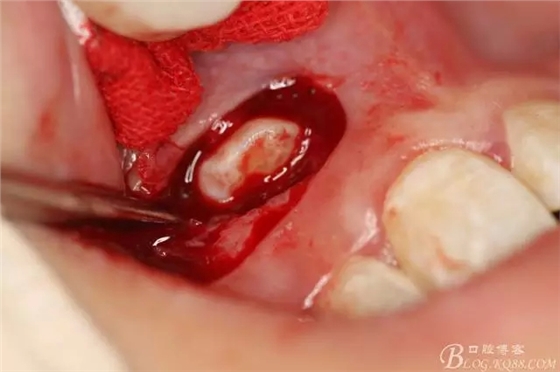

病例資料: 患者、柴xx、女、16歲。??茩z查及病歷如下圖: 患者同意我院正畸科建議,遂轉(zhuǎn)診倒外科。術(shù)前簽知情同意書。 治療過程: 圖1.術(shù)前的CBCT檢查:13阻生,疑為含牙囊腫。縱剖面顯示12牙根吸收至根尖1/3。 圖2.局部麻醉下 。行唇側(cè)弧形切口,12松動不到1°。 圖3.翻瓣、暴露骨面。 圖4.去骨、 暴露13牙冠 圖5.去骨、逐漸顯露13。 圖7.拔除13. 圖8.摘除囊壁 圖9.必須完整剝離囊壁。 圖10.摘除囊壁后形成的骨腔 圖11.超聲骨刀12根尖倒預(yù)備 圖13. 消毒棉球骨腔內(nèi)隔濕血液,紙尖干燥倒預(yù)備好的根管 圖14. 紙尖無血即可 圖15。MTA倒充填 圖16.骨腔填塞膠原蛋白海綿 圖17.拔除的13及摘除的囊壁 圖18.縫合 圖19.術(shù)后x線根尖片影像:MTA封閉根尖